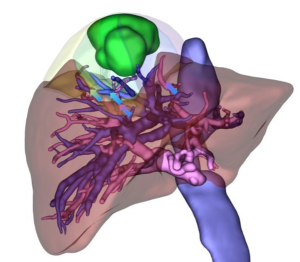

術前3Dシミュレーション

肝臓内は血管や胆管が複雑に入り組んでいます。当院では、それらと腫瘍との位置関係を正確に把握するために術前に3D画像を作成し詳細な検討を加えています。これにより安全な切除範囲の判断や手術時間の短縮を図るとともに、重要な血管の損傷を回避し出血量を低減化するなど、安全で質の高い手術を提供しています。